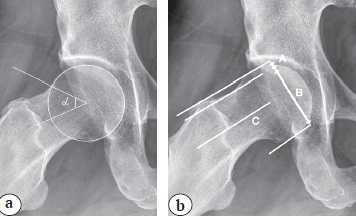

Рентгенологическая диагностика нарушения сферичности головки бедренной кости. В 2002 г. H.P. Nötzli с соавторами предложили метод определения деформации головки бедренной кости с использованием коронарного среза МРТ [45]. Однако этот метод применим и для рентгенограмм [46]. Сферичность головки рассчитывается путем измерения угла между линией, проведенной через центр шейки и головки бедренной кости, и второй линией, проведенной от центра головки бедренной кости к точке окончания сферичности головки, где начинается выступающая часть с большим радиусом (R), чем радиус (r) головки. Угол сферичности назван углом альфа (a), и в литературе приводятся различные его значения в норме (рис. 4).

Рис. 4. Определение угла α

Fig. 4. Determination of the α angle

H.P. Nötzli с соавторами определили среднее нормальное значение угла a в 42°, C.W. Pfirrmann с соавторами и J. Zhou с соавторами — в 55° [47, 48]. K.K. Gosvig с соавторами рекомендовали определять не только нормальный угол a, но и пограничные значения, при которых в сочетании с другими факторами возможно проявление клинической картины импинджмента [49]. Нормальный угол a был определен для мужчин равным или меньше 68°, для женщин — 50°. Пограничные значения были определены от 69° до 82° для мужчин и от 51° до 56° для женщин. Некоторые исследования выявляют значительное совпадение между диапазоном значений угла a как у пациентов с симптомами ФАИ, так и в контрольной группе без клинических проявлений [50] или показывают относительно слабую дифференцировку симптоматической и бессимптомной групп в зависимости от угла a, определяя средние значения в группе сравнения равными 47,0±2,0°, а в группе с клиническими проявлениями — 67,4±8,0° [51].

Выполнение cтандартной укладки по Dunn 45° подразумевает сгибание в бедре под углом 45°, отведение на 20° и нейтральное положение стопы [54, 55, 56]. Однако в литературе зачастую выполнение укладки по Dunn 45° в классическом варианте заменяется на выполнение этой укладки с ротацией 40°. При сгибании в ТБС на 45° и наружной ротации бедра на 40° выявление деформации улучшается [57]. Иногда возникает ситуация, когда при измерении угла a мы получаем значение меньше 50–55°, однако визуально можно определить снижение сферичности головки бедренной кости (рис. 6 а). В этой ситуации будет полезно измерение офсетного коэффициента (отношение расстояния между параллельными линиями оси шейки, которые проводятся по краю шейки и краю головки бедренной кости к диаметру головки), величина которого в норме должна быть более 0,17 (рис. 6 b) [56]. Значение менее 0,17 говорит о наличии cam-деформации.

Рис. 6. Измерение офсета головки/шейки бедренной кости:

a — измерение угла a, составляющего 51°;

b — определение офсетного коэффициента, составляющего 0,09

Fig. 6. Measurement of femoral head/neck offset:

a — a angle measurement of 51°;

b — determination of offset ratio, which is 0.09